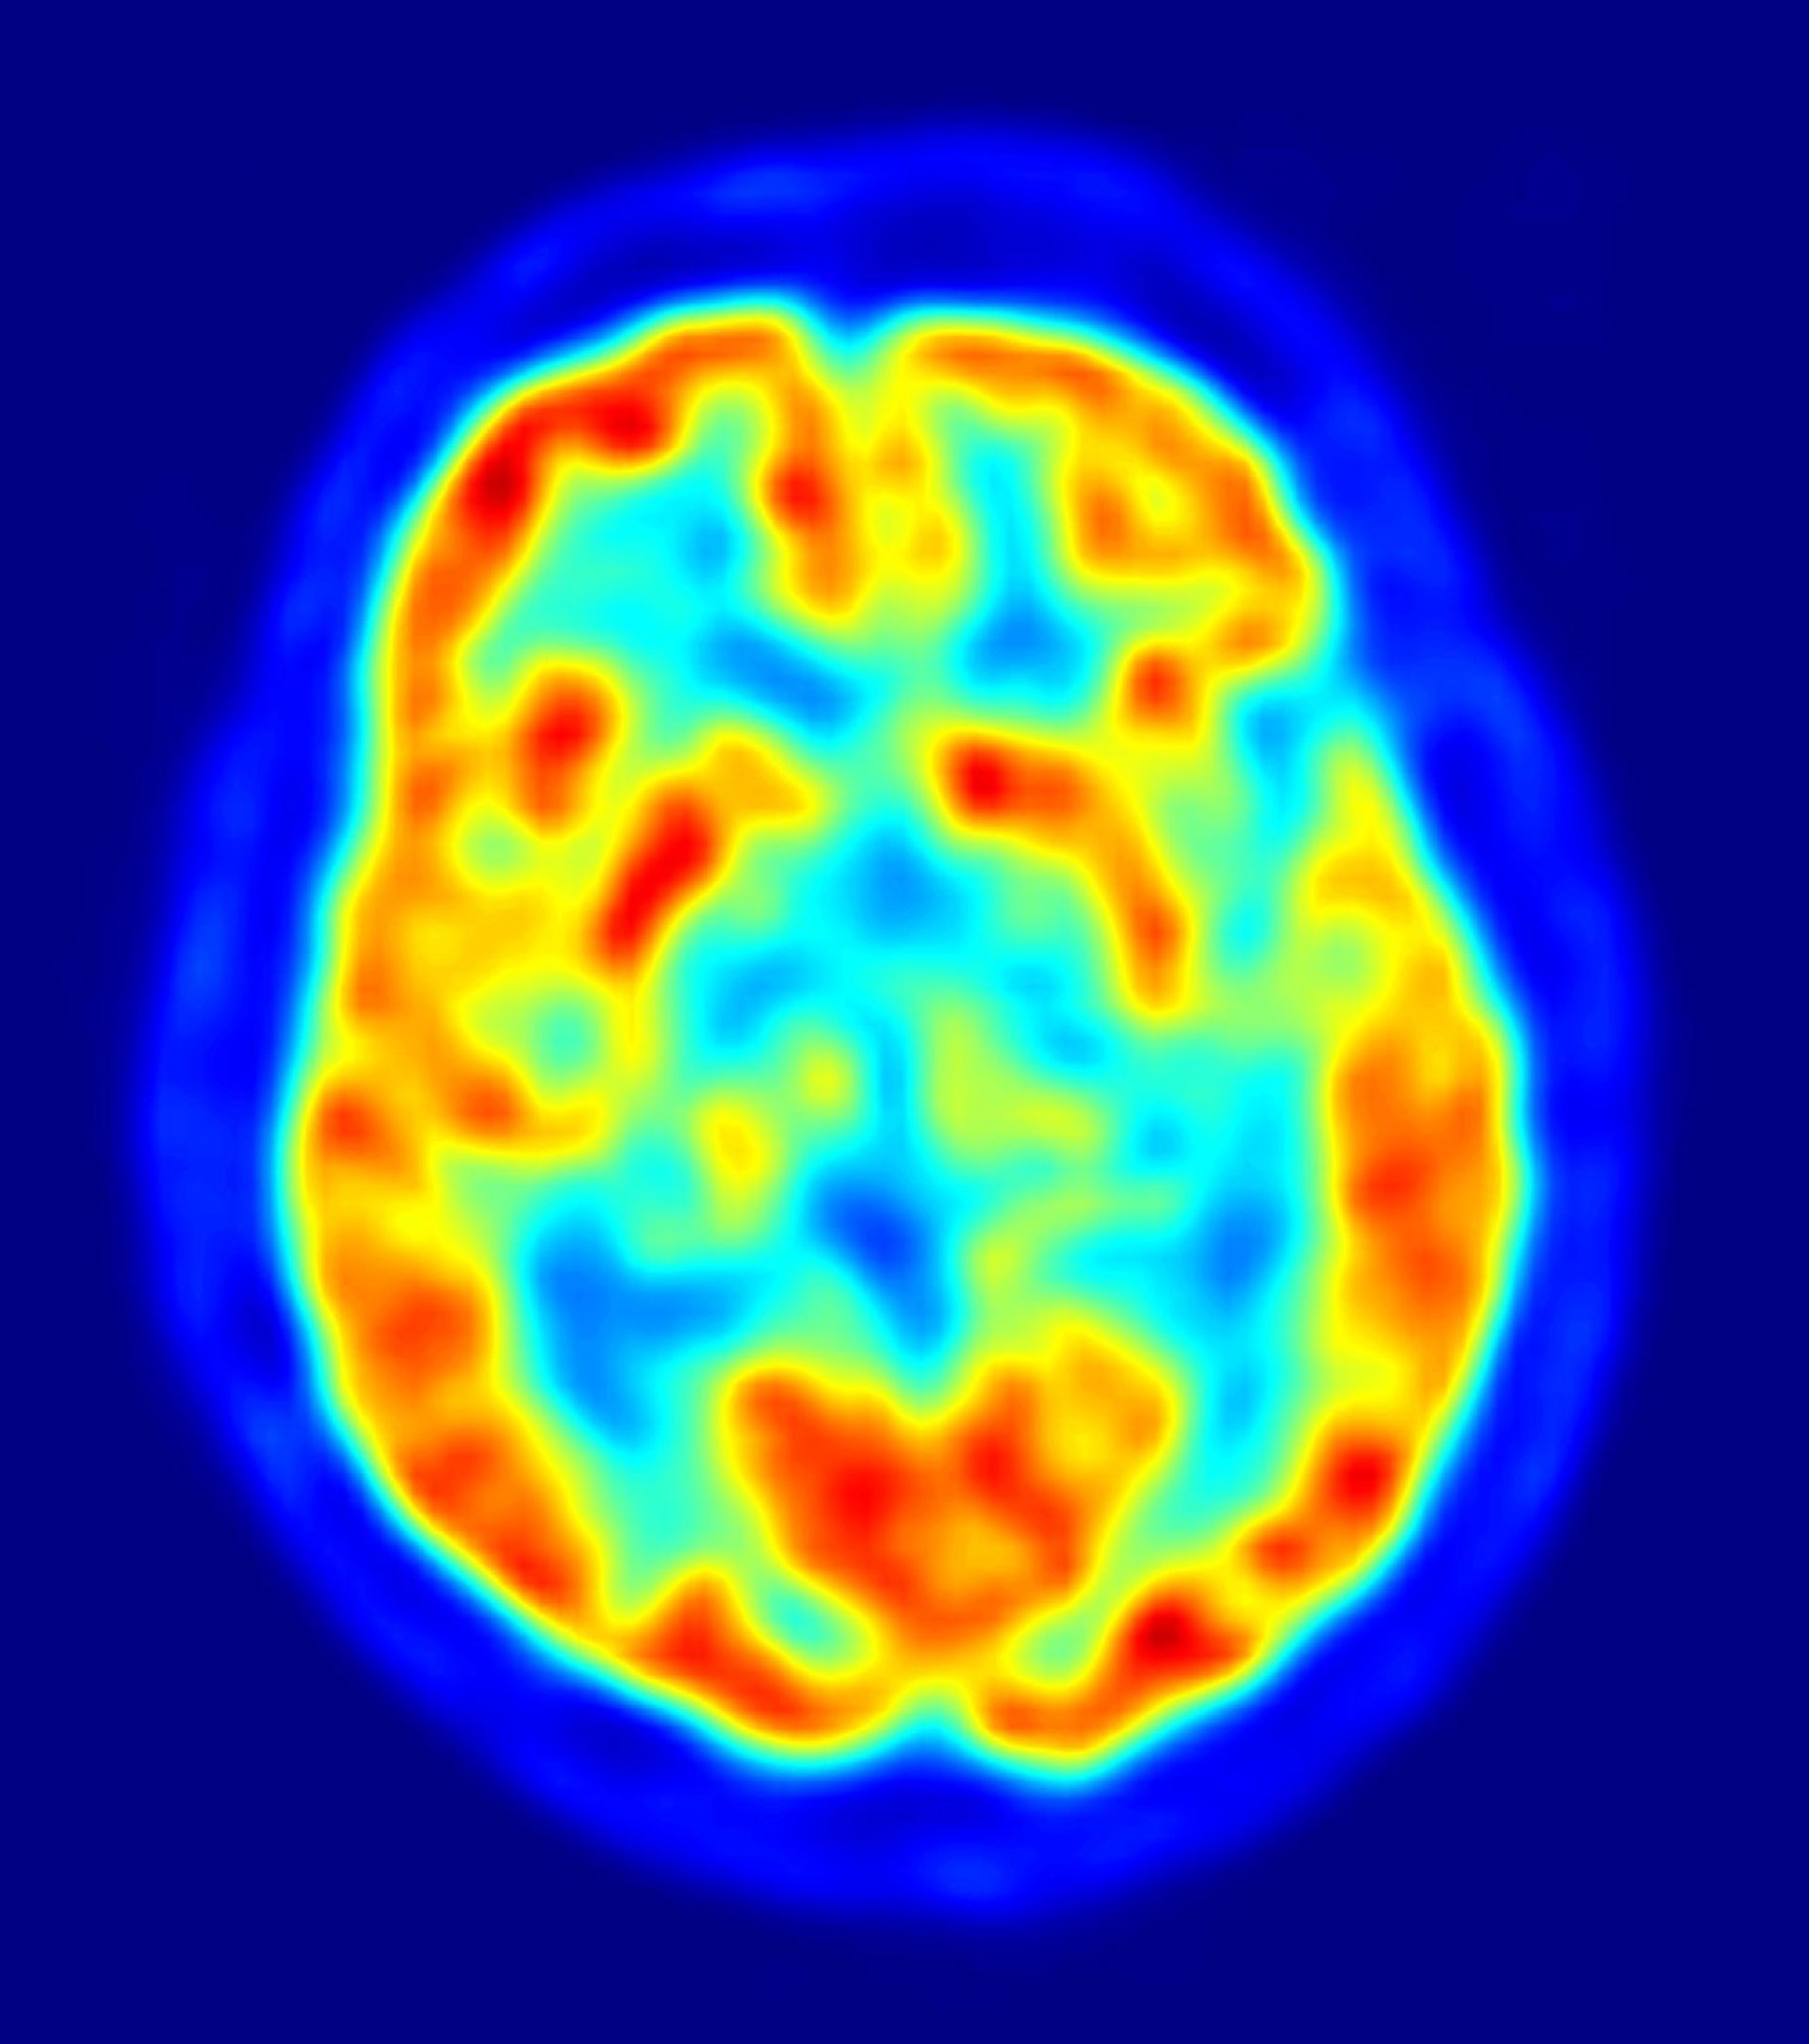

Investigadores de la University of North Carolina (UNC), en Chapel Hill (Estados Unidos) han descubierto, a través de técnicas de imagen por resonancia magnética, diferencias importantes en el desarrollo cerebral que comienza a los seis meses de edad en niños de alto riesgo que después desarrollaron autismo, en comparación con los menores de alto riesgo que, finalmente, no padecieron la enfermedad.

A los 24 meses, 28 niños (30%) reunían los criterios para diagnosticar un desorden del espectro autista, mientras que 64 menores (70%) no los cumplían. Los dos grupos se diferenciaban en el desarrollo de la extensión de las fibras de materia blanca --las vías que conectan las regiones cerebrales-- medidas por anisotropía fraccional (FA).

La FA mide la organización y el desarrollo de la materia blanca, en base al movimiento de las moléculas de agua en el tejido cerebral. El estudio examinó 15 extensiones de fibras diferentes y encontró significativas diferencias en las trayectorias FA en 12 de 15 extensiones entre niños que desarrollaron autismo frente a menores que no lo hicieron.

Los menores que desarrollaron la enfermedad presentaban FA elevada a los seis meses, pero después experimentaban cambios más lentos en el tiempo. A los 24 meses de edad, los niños con autismo tenían menores valores de FA que los niños sin autismo. Para Wolff, "esta evidencia, que implica múltiples vías de fibra-- sugieren que el autismo es un fenómeno que afecta a todo el cerebro, no de forma aislada a ninguna región en particular".